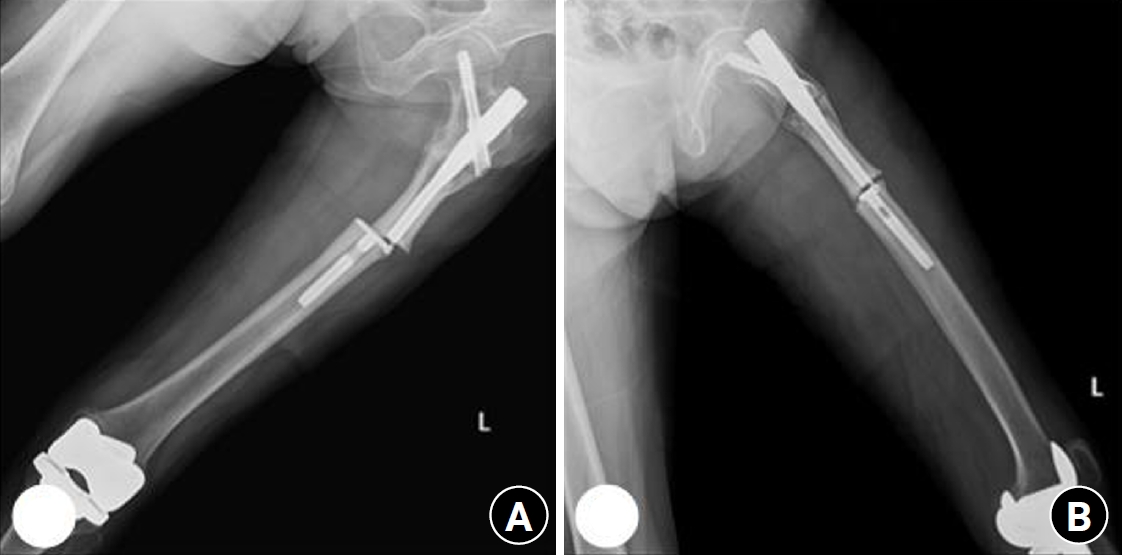

Fig. 5.

Radiographs of the same patient with a proximal one-third fracture of the left femur. (A) Anteroposterior view. (B) Lateral view.

Fig. 4.

Prefracture radiograph of an 8-year-old female patient who presented with a proximal one-third fracture of the left femur (bilateral lower-extremity standing anteroposterior view).

Case 2: osteogenesis imperfecta

An 8-year-old female patient visited our emergency room complaining of pain in the left thigh that began on the day of her visit. She slipped and directly injured her thigh upon falling to the left. Initial examination revealed normal laboratory findings, including serum calcium levels of 9.0 mg/dL and inorganic phosphorus levels of 4.7 mg/dL. Radiographic evaluations, including anteroposterior and lateral views of the left femur, demonstrated a transverse irregular fracture line in the proximal one-third area of the left femur, accompanied by lateral cortex hypertrophy. Importantly, the possibility of malignancy or infection as contributing factors to the fracture was considered low. Two years prior, the patient had visited the pediatric department of our hospital due to concerns about her height, which was below that of her peers. Following genetic testing, she was diagnosed with osteogenesis imperfecta and has since been monitored by both the pediatrics and orthopedics departments. At that time, lateral bowing of both femurs was observed in both lower extremities during standing anteroposterior evaluations (Figs. 4, 5). She had previously undergone epiphysiodesis on both femurs due to genu valgum. After diagnosis, the patient underwent open reduction and internal fixation using an ender nail. Follow-up evaluations indicated successful bone union at the fracture site.